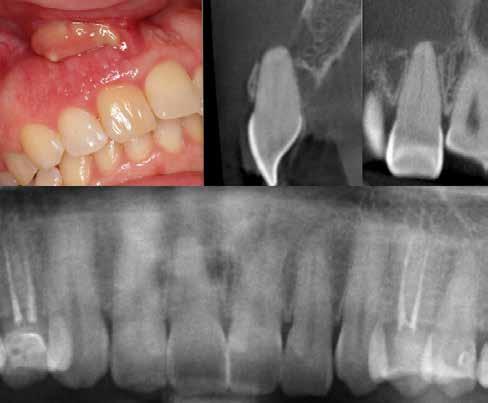

1. a–g. ábrák: A direkt pulpasapkázás lépései. Kiindulási bitewing-felvétel: A meglévő restaurátum közel helyezkedett el a pulpakamrához (a). Kiindulási periapicalis felvétel: Nincs periapicalis elváltozás fennállására utaló jel (b). A pulpaexpozíció (c). A vérzéscsillapítás céljából 20 másodpercen keresztül steril vattagombóccal történő kompressziót követően látható pulpaseb (d). A pulpasapkázás céljából behelyezett anyag, a széli részek tisztázása előtt készült felvétel (e). A röntgenárnyékot nem adó ideiglenes tömés behelyezése után készült felvétel (f). Az első ülés végén a röntgenárnyékot nem adó ideiglenes töméssel ellátott fogról készített röntgenfelvétel (g).

2. ábra: A hat hónapos kontroll alkalmával készített röntgenfelvételen vastag dentinhíd látható a pulpasapkázó anyag alatt.

3. ábra: A hároméves kontroll alkalmával készített röntgenfelvételen megfigyelhető a restaurátum pontos illeszkedése.

Esetbemutatás (1.)

Egy 35-éves férfi beteg akut ellátás céljából kereste fel rendelőnket. A jobb felső második kisőrlő (15) fogát érő hideg inge-

6. a–d. ábrák: A bal alsó második nagyőrlőfogon (3.7) kialakított konzervatív hozzáférési nyíláson keresztül végzett endodonciai kezelés lépései. A mezialis gyökér jelentős mértékben görbült. A gyökértömés hidraulikus kondenzációs technikával készült.

rekre jelentkező, rövid ideig tartó éles fájdalomra panaszkodott.

A diagnózisunk reverzibilis pulpitis volt. Periapicalis elváltozás jelenlétét nem vélelmeztük. A fogban lévő amalgámtömés eltávolítása során körülbelül egy 3 mm átmérőjű pulpaseb keletkezett a buccalis pulpaszarvnak megfelelően (1. a–g. ábrák) Mivel nem tapasztaltunk jelentős vérzést, és a diagnózisunk reverzibils pulpitis volt, ezért a direkt pulpasapkázás elvégzése mellett döntöttünk.

A kavitást 2,5%-os nátrium-hipoklorit oldattal fertőtlenítettük, majd sűrű konzisztenciájú kalcium-szilikát alapú anyagot (CeraPutty, Meta Biomed) készítettünk elő a direkt pulpasapkázás elvégzéséhez. Az első kezelés végén röntgenárnyékot nem adó ideiglenes töméssel (NexTemp LC, Meta Biomed) zártuk

az üreget annak érdekében, hogy a direkt pulpasapkázásra használt anyag megfelelő pozícióját radiológiailag ellenőrizni tudjuk. A második ülés során kompozit tömőanyagból (Ezfil, Meta Biomed) direkt adhezív restaurátumot készítettünk.

A kezelést követően a beteg tünetmentes volt. A kérdéses fog a kontrollvizsgálatok során végzett szenzibilitástesztekre fiziológiás reakciókat adott. A hat hónapos kontroll alkalmával készített röntgenfelvételen a sérülésnek megfelelően széles dentinhidat észleltünk (2. ábra). A restaurátum a hároméves kontroll során is megfelelőnek bizonyult (3. ábra)